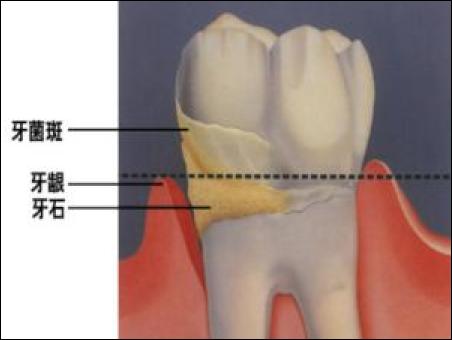

牙齒附著在牙槽骨上,外面包裹著牙齦。當牙周袋形成后,牙菌斑就會寄居于此,在牙菌斑細菌的作用下就會不斷地發(fā)炎,一方面它會侵蝕牙槽骨,讓牙槽骨慢慢地吸收;另一方面,牙齦腫脹發(fā)炎會降低牙齦與牙齒的附著力,兩種合力共同作用的結果,就是牙齒會越來越松動,直到失去固有的功能。

2、好好的牙齒為什么會形成牙周袋?